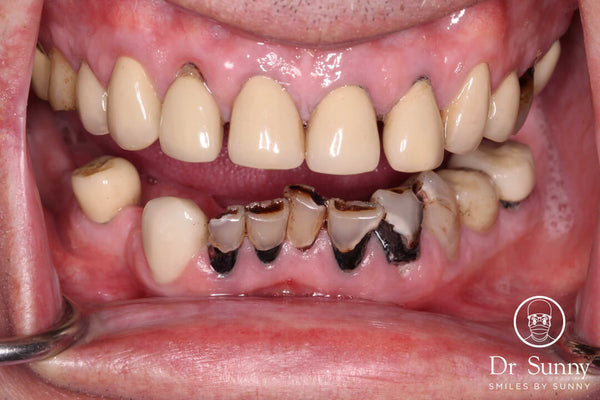

Extremely difficult lower anteriors

Introduction: This case was completed by Dr. Sunny (@smilesbysunny) from the UK. He offers one day courses (@drecomposite) in the UK covering the Greater Curve technique. Dr. Sunny acknowledges he can... Read More